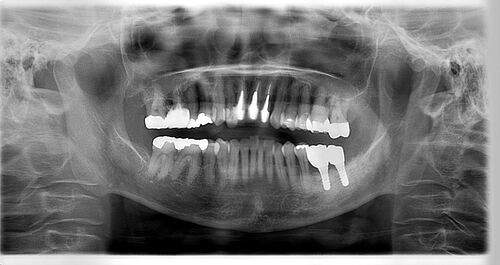

レントゲン写真

- 透過像

| 年齢 | 50代・男性 |

| 主訴 | 右下歯が疼く |

| 治療内容 | ・右下6番インプラント ※1:FGG(遊離歯肉移植術)とは、足りない歯ぐきを上顎から上皮を切り取り移植する外科手術 |

| 治療費 | 合計:902,000円(税込) ■内訳 |

| 治療期間 | 9ヵ月 |

| 治療方針 | 右下の当該歯は歯根破折により保存不可能と診断しました。歯周疾患も伴っていたため抜歯後に骨吸収※1が大きく起こることが予測できました。チタンメッシュ併用骨再生誘導法(GBR※2)を選択しインプラント埋入と同時に行い自然な歯槽骨のラインを再現しました。またGBRを行う際にインプラント辺縁の付着歯肉の減少が起こる為、遊離歯肉移植術(FGG※3)を行い清掃性を考慮した形態に仕上げました。 ■治療方針の解説 治療した右下の歯をレントゲンで撮影したところ根本の部分に黒く写る箇所があり「根尖性慢性周囲炎※1」と診断。また歯周病も進行していました。 ※1 骨吸収・・・歯槽骨という歯を支える骨がなくなっていくこと |

| 担当者所見 | 主訴の右下だけでなく歯茎の腫れ、発赤があり不良補綴や不良充填など他にも治療箇所が多数ありました。プラークコントロールが不良であった為まずはブラッシング指導を行いセルフケアの重要性を理解していただくところからスタートしました。 右下6番の歯はインプラント治療を行なった結果審美的にも機能的にも患者様の満足を得ることができました。骨造成と歯肉移植も行なった為インプラントを支える十分な歯周組織の獲得ができたと思っております。 |